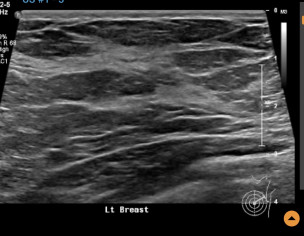

Left breast ultrasound report said no concerns. Symptoms - enlarged lymph nodes left breast, small cyst, changes in size and shape of left breast, dimples in lower left breast, pain in outer quadrant of left breast. Second opinion on ultrasound pics?